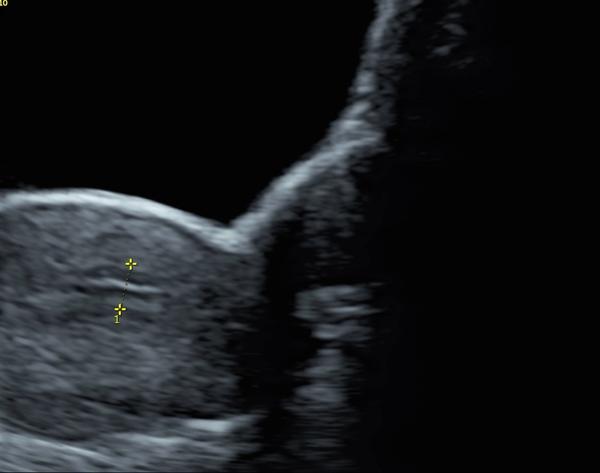

Co znamená čárka na ultrazvuku? Prosím o radu

Víte prosím někdo co to je ta čárka? Díky

Jedná se o ultrazvuk dělohy, břicha to černé je močový měchýř zřejmě